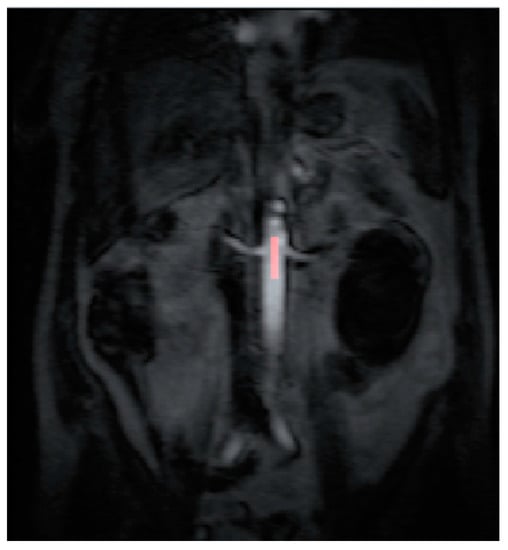

2.4. Data Post Processing

All the MR images were anonymized and post processing was performed offline by a single consultant radiologist with greater than 10 years of clinical experience (Dr Tze Min Wah). Images were uploaded into PMI 0.4 (Platform for Research in Medical Imaging Version 0.4 [13], which was running on a desktop PC. A standardized 4-voxel region was used to extract an arterial input function (AIF). This region of interest (ROI) was drawn inside the aorta at the approximate level of the origin of the vascular pedicles of the kidneys (Figure 1 and Figure 2).

Figure 4. The ROI is drawn on the maximum concentration map generated by PMI software after radiofrequency ablation treatment.